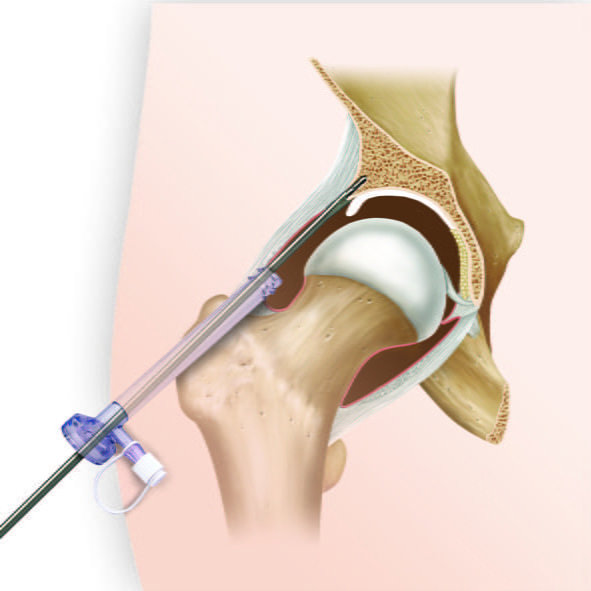

Устранение кистозной опухоли тазобедренного сустава происходит с применением артроскопа.